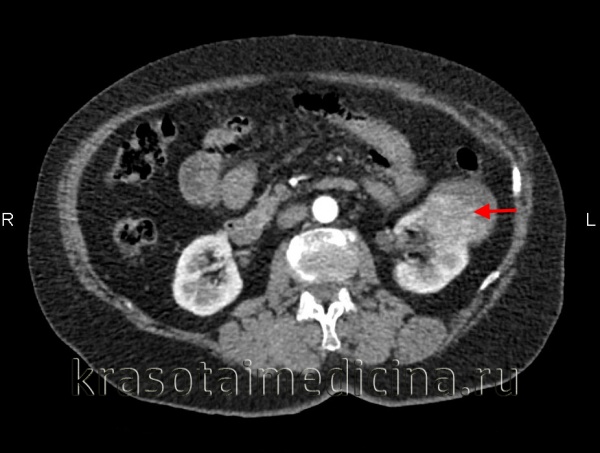

- Томографическое исследование. КТ почки контрастным усилением позволяет обнаружить рак почки любого размера, установить его структуру и локализацию, глубину прорастания паренхимы, инфильтрацию паранефральной клетчатки, опухолевый тромбоз почечной и нижней полой вен. При наличии соответствующих симптомов проводится КТ органов брюшной полости, забрюшинного пространства, костей, легких и головного мозга с целью выявления метастазов.